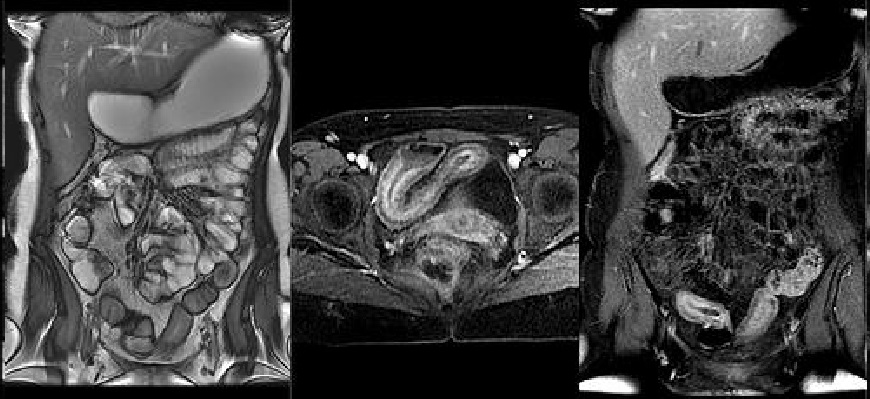

A continuación puedes consultar información general acerca de algunos de los estudios de Resonancia Magnética que tenemos disponibles, solamente da un clic en la imagen deseada: